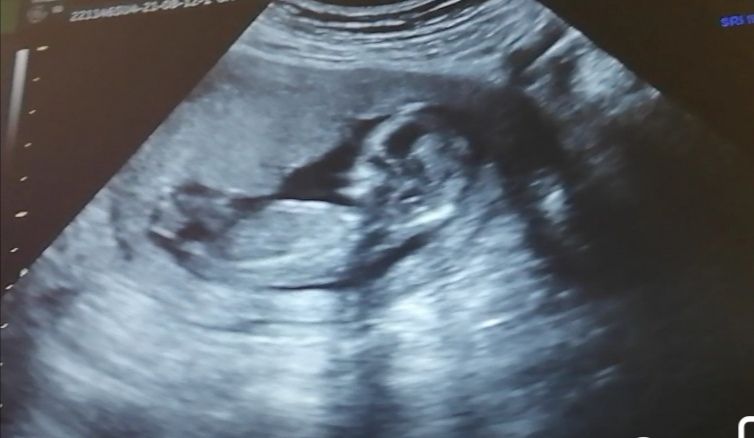

На нижнем, если это бугорок, то что я за него принимаю, то девочка

Так если доктор не увидел, почему вы считаете, что смогут увидеть тут?) Полового бугорка действительно на фото не видно, но по форме головы предположу мальчика) Предположение, не более)

Пол малыша на сроке 12–13 недель Порекомендуйте врача УЗИ